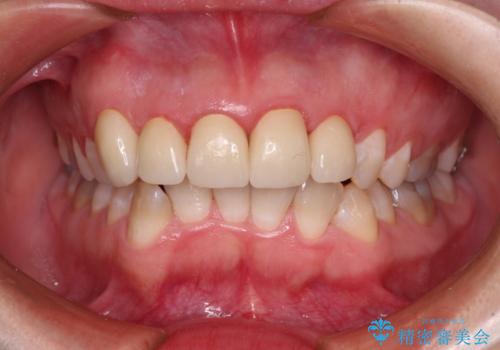

- 歯列不正を改善する目的で装着した前歯のセラミックが気になるとのことで来院された患者様です。

金属の裏打ちを用いたセラミッククラウンであったため歯肉縁に黒ずみが見えてくることは良くありますが、全体的に歯列が不揃いであることが気になったので、それらをオールセラミッククラウンにて改善することとしました。

セラミッククラウンが外れてしまうことを心配して、歯ブラシをあまり当てられなかったとのことで、歯肉に軽度の炎症が認められました。

オールセラミッククラウン装着後、レントゲン写真より精度良く装着されていることは確認できているので、日頃のブラッシングで改善させるよう指導しています。